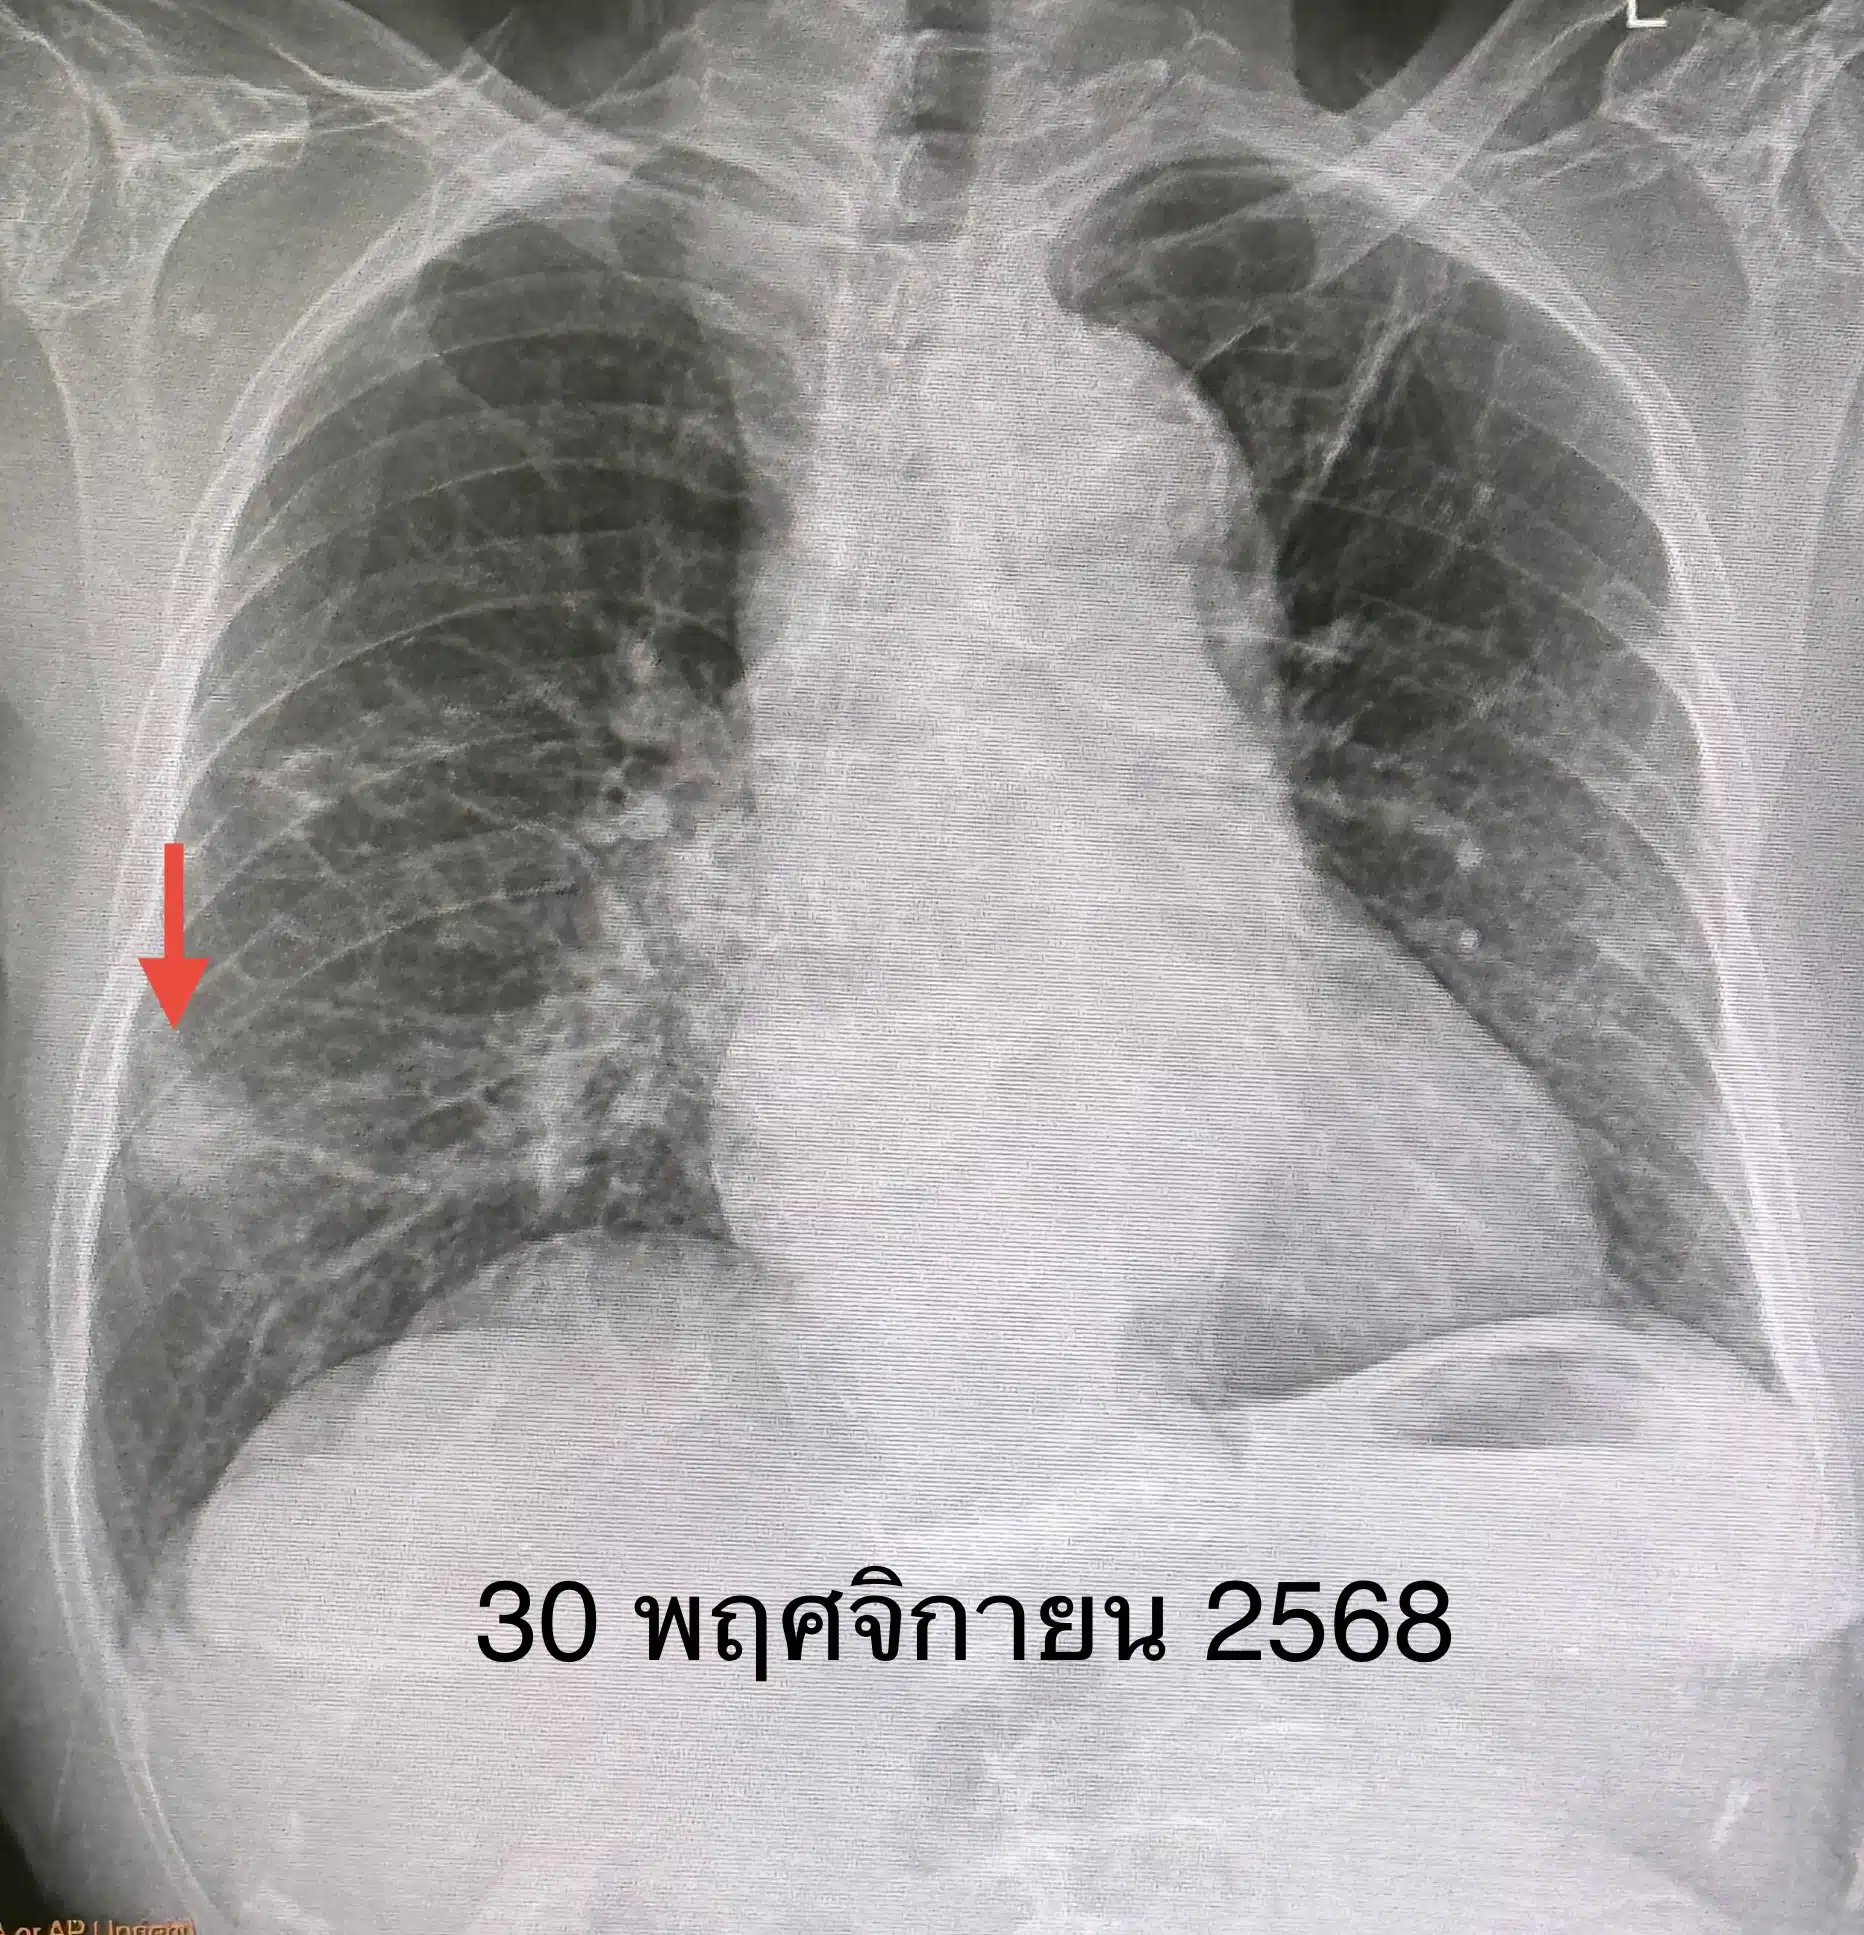

แต่ผลการตรวจทางแพทย์กลับพบความผิดปกติ ซึ่งภาพเอกซเรย์ปอด พบเงาผิดปกติที่ปอดข้างขวาด้านบน (รอยโรคเดิมจากวัณโรค) แต่สิ่งที่น่ากังวลคือ พบก้อนเนื้อใหม่ขนาด 1.9 x 1.9 เซนติเมตร ที่ปอดข้างขวาด้านล่าง ปีก่อนหน้านี้ไม่เคยมี จากเอกซเรย์คอมพิวเตอร์ (CT Scan) พบก้อนขนาดใหญ่ขึ้นเป็น 3.0 × 2.4 × 2.0 เซนติเมตรที่ปอดขวาด้านล่าง ส่วนผลเลือดค่าบ่งชี้มะเร็งทุกตัวปกติ